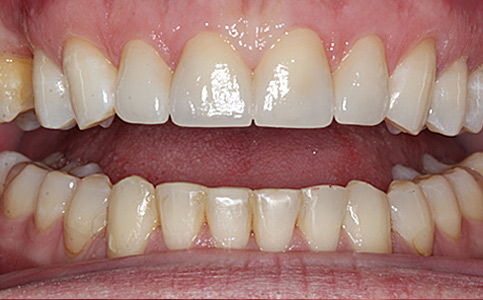

Przykład pełnej rehabilitacji protetycznej obejmujący leczenie biologiczne, uzupełnienie braków zębowych implantami oraz korony pełnoceramiczne w łuku górnym i dolnym. Spektakularna metamorfoza uśmiechu wykonana przez zespół Centrum Stomatologii i Ortodoncji FRESHmed odmieniła życie Pacjenta dodała pewności siebie i sprawiła, że z chęcią się uśmiecha.